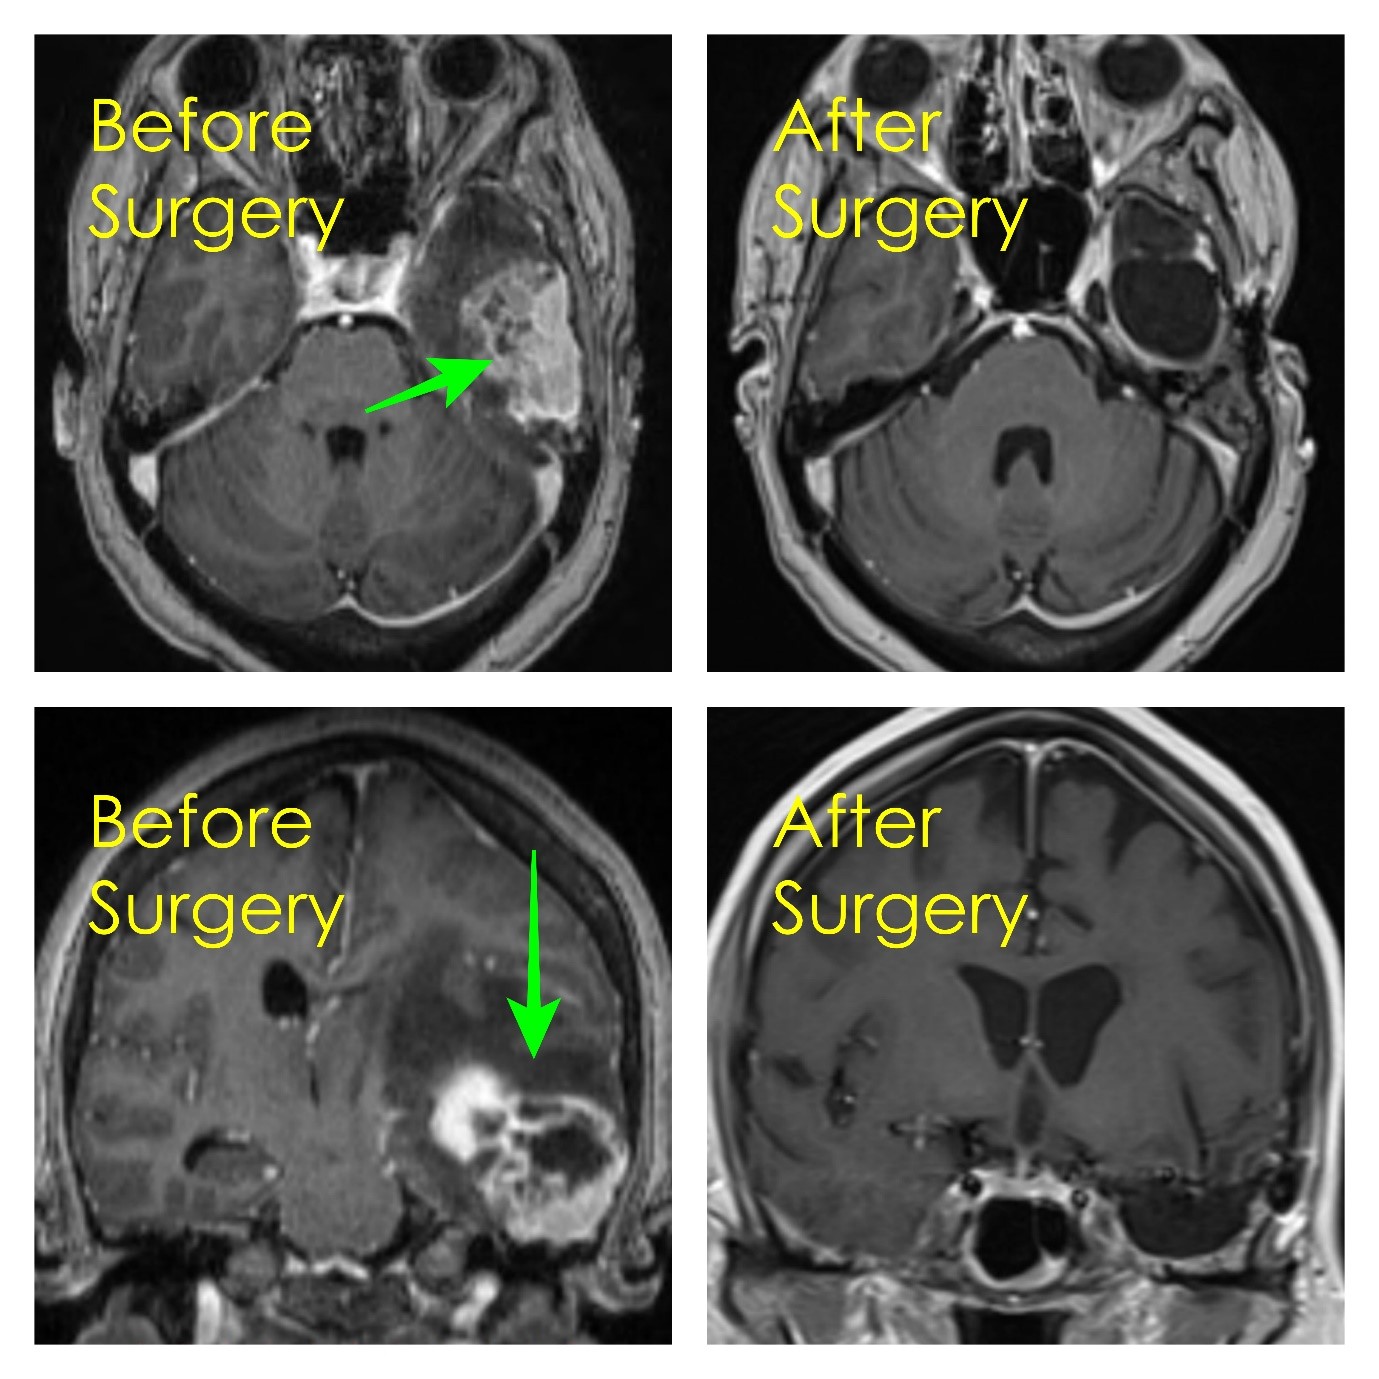

Understanding the differences between craniectomy vs craniotomy is vital for neurological care. This guide compares these surgical procedures, detailing how they address brain swelling, intracranial pressure, and traumatic injuries. Learn about the recovery process, surgical techniques, and clinical indications for each intervention to help you navigate critical neurosurgical decision-making and patient outcomes effectively.

Read full article: Craniectomy Vs Craniotomy